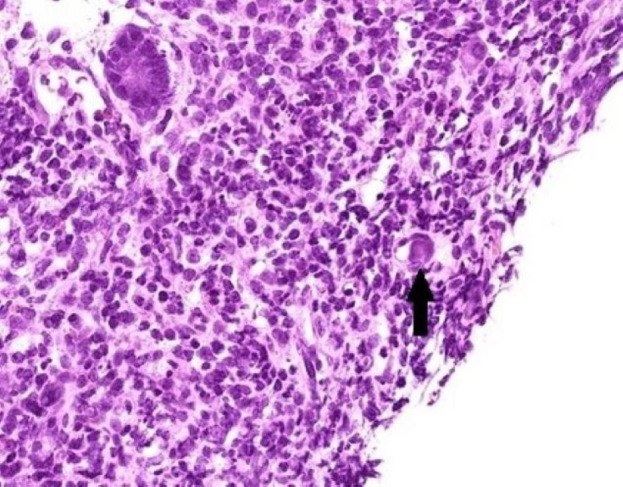

Methods: We retrospectively reviewed children<6 years of age with intussusception who underwent surgery for failed reduction. The pathological tissue was processed into formalin-fixed paraffin-embedded (FFPE) sections. Adenovirus immunohistochemistry (IHC) and PCR testing were performed to obtain direct evidence of the relationship between adenovirus infection and intussusception.

Results: Our study included 29 patients, 27 appendiceal and 8 intestinal tissues. Only eight appendix specimens were successfully processed into FFPE tissue. IHC testing was positive in three cases (37.5%), and PCR testing was positive for adenovirus type C in four cases (50%). The control group consisted of eight children <6 years who underwent incidental appendectomies, and all control subjects had negative IHC and PCR analyses. PCR is as useful and reliable as IHC in diagnosing adenovirus in intussusception and has greater sensitivity than IHC.

Conclusion: We directly confirmed the relationship between adenovirus infection and intussusception through IHC analysis and PCR detection of pathological evidence. PCR is more sensitive than IHC for diagnosing adenovirus in intussusception.